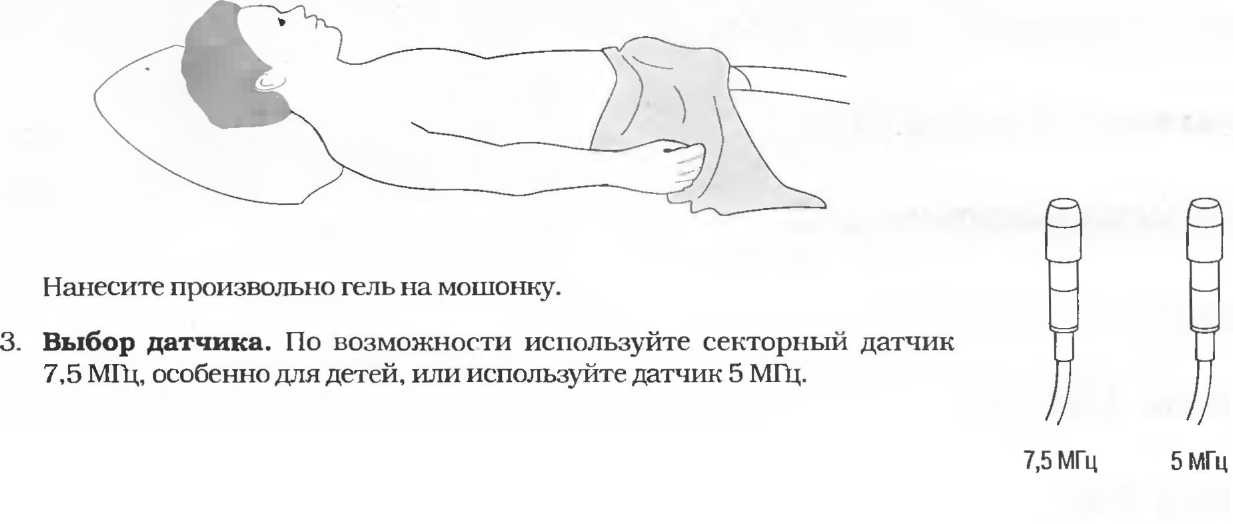

3. Ультразвуковые исследования в педиатрии. Для детей необходим датчик с частотой 5 МГц с глубиной фокусировки на 5-7 см. При исследовании мозга новорожденного используется секторный датчик с частотой 7,5 МГц с глубиной фокусировки на 4-5 см (этот датчик также используется для исследования яичек и структур шеи у взрослых).